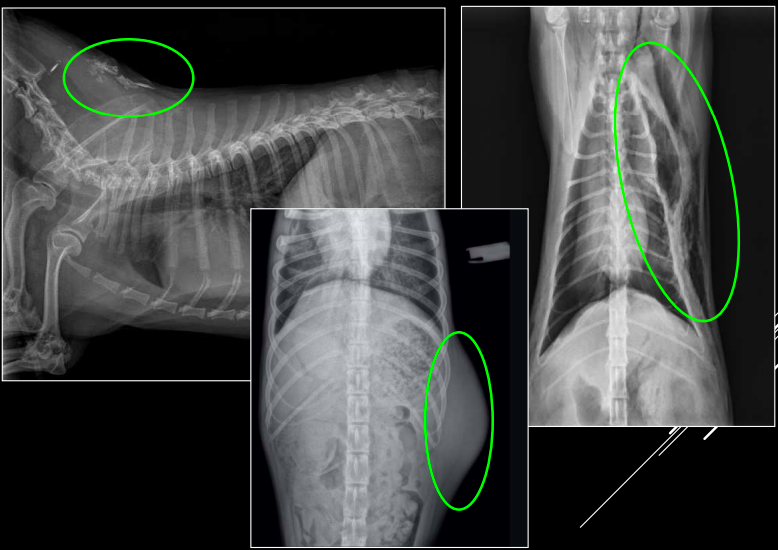

CLASIFICACIÓN DE MASAS MEDIASTÍNICAS

-

Craneodorsales: alteraciones esofágicas, aneurisma aórtico, hematoma, tumor base cardíaca/neurogénico, absceso, granuloma, lesión vertebral.

Desplazamiento traqueal ventral por neumoesofago

Desplazamiento traqueal dorsal por masa en el mediastino craneal

Hiliares/Perihiliares: alteraciones esofágicas, tumor base cardiaca, linfoadenopatía traqueobronquial, masa tiroidea ectópica.

Masa de opacidad tejido blando que desplaza la traquea y la bifurcación bronquial.

Puede ser por los nodulos parabronquiales, esofagico o por masa en el pulmón

Caudodorsales: hernia paraesofágica, tumores neurogénicos, granulomas.

Clase del 14/10

Craneoventrales: linfoma, timoma, tumor tiroideo, histiocitosis, lipoma, fibrosarcoma, linfoadenopatía esternal o craneal, absceso, aneurisma auricular.